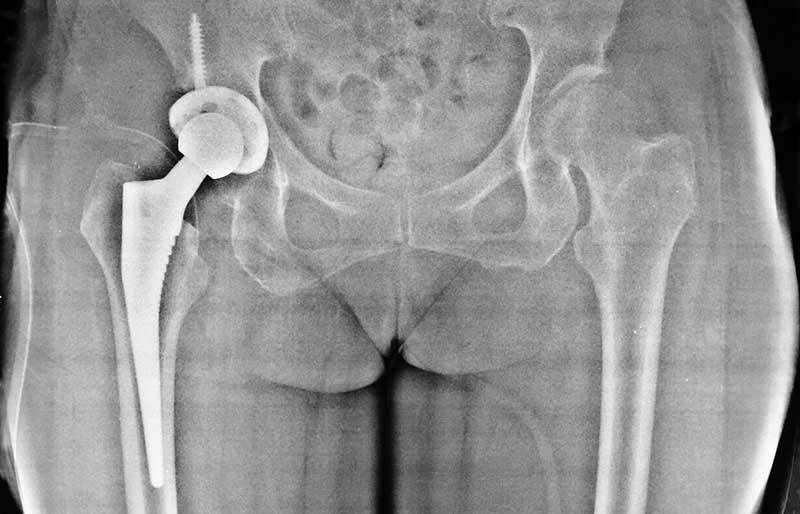

Operasi Penggantian Sendi Panggul

Operasi penggantian sendi panggul adalah suatu operasi untuk mengganti sendi panggul yang rusak dengan sendi buatan yang disebut prosthesis. Penyebab utama kerusakan sendi panggul adalah osteoartritis (baca penjelasan tentang “Osteoartritis”) dan sendi panggul adalah sendi terbanyak kedua setelah lutut yang terserang penyakit ini.